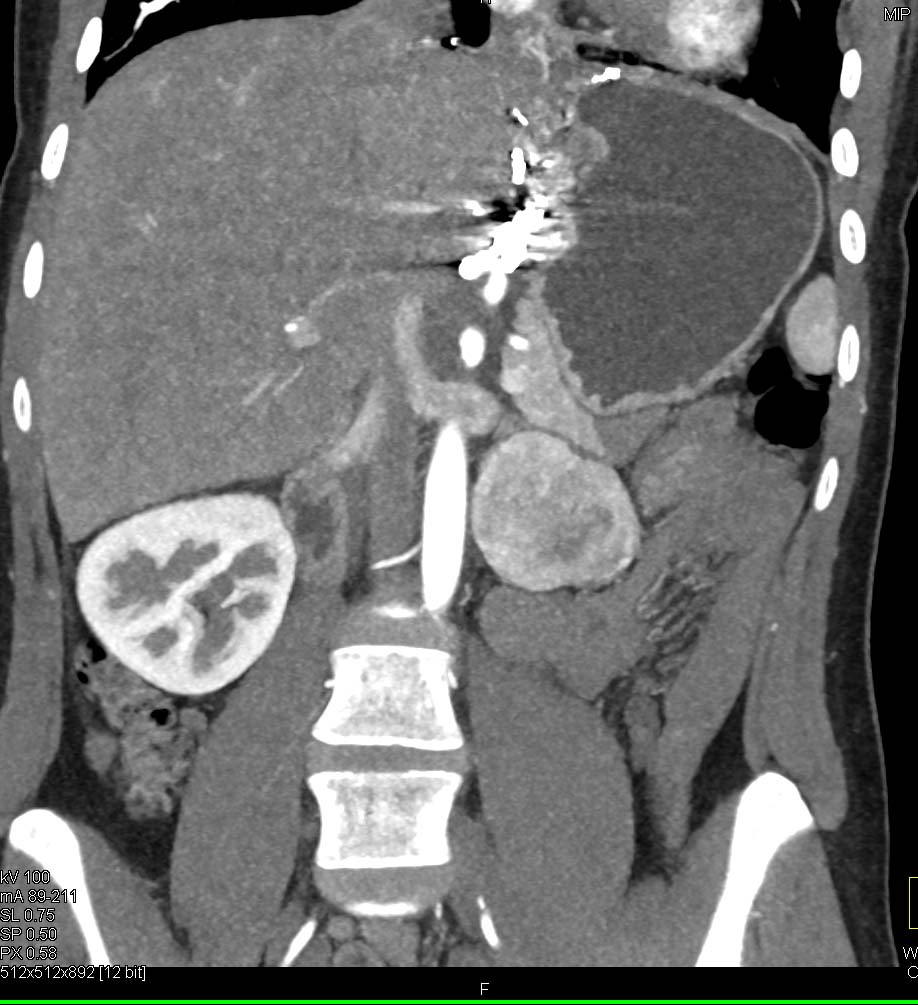

The most likely diagnosis in this case is?

lymphoma

Castleman disease

melanoma

paraganglioma